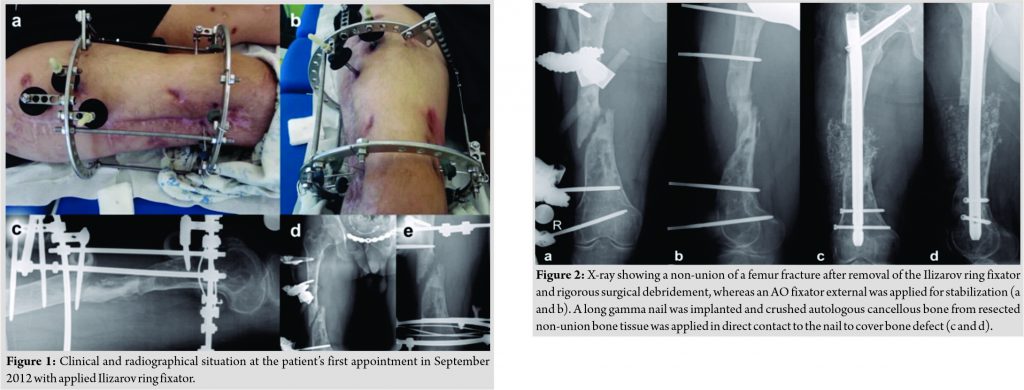

A 24-year-old patient was admitted to our department due to a car accident with multiple injuries, including femur fractures of both sides which were treated with plate osteosynthesis in Belarus. No complication was apparent on the left side. However, a persistent wound secretion with subsequent osteomyelitis was present on the right side 3 years after initial surgery even after adequate surgical debridement and antibiotic regime. Biopsy revealed methicillin-resistant and borderline oxacillin-resistant S. aureus (BORSA). X-rays confirmed osteomyelitis with a sequestrum, a fistula, and significantly reduced bone stock. The patient presented with an Ilizarov ring fixator in situ in our department for the 1st time in 2012. The Ilizarov ring fixator was implanted in Belarus in 2011. The patient preferred an exceptional salvage procedure to preserve the limb since amputation was not an option (Fig. 1). Therefore, we suggested a two-step-surgery approach to treat the osteomyelitis before performing the definitive osteosynthesis. The Ilizarov ring fixator was removed and a vigorous debridement was performed by refreshing the pseudarthrosis, removing the sequestrum, and dead bone. Finally, an AO fixator external was implanted after several efficient debridements (Fig. 2a and b).

An antibiotic therapy was established with vancomycin (20 mg/kg/d) for 4 weeks followed by clindamycin (1800 mg/d) and co-trimoxazole forte (sulfamethoxazole 2400 mg/d/trimethoprim 640 mg/d) for 6 weeks. Ciprofloxacin (1500 mg/d) was additional given for the first 2 weeks during the treatment with clindamycin. The AO fixator external was removed after 10 weeks of antibiotic treatment and surgery was performed after an additional antibiotic-free window of 5 weeks. We decided to perform a definitive treatment without intraoperative local antibiotic carrier application since the laboratory blood test revealed no elevated infection parameters. Moreover, no signs of persistent infection were found during the operation. The bone defect was stabilized by a long gamma trochanteric nail (Stryker, UK). A wide resection of the non-union tissue was performed which was crushed and placed beside the nail to bridge the defect zone (Fig. 2c and d). Surprisingly, biopsies of the proximal and distal non-union side revealed the same bacteria and resistogram when compared to the initial biopsies taken before the rigorous debridement procedures (Table 1). However, reimplantation of crushed bone tissue from the infected side did not result in a relapse of osteomyelitis. The most likely bacteria load was reduced and the local effect of antibiotics was improved by crushed bone even when used from non-union infected side. Antibiotic therapy was established with vancomycin (20 mg/kg/d) for 2 weeks followed by co-trimoxazole forte (sulfamethoxazole 2400 mg/d/trimethoprim 640 mg/d) for 10 weeks. Neoangiogenesis proceeds much faster in small autologous fragments as in large dimensioned bone stock. Therefore, the blood supply increased around the affected area along with the bioavailability of antibiotics. Frequent radiographic and clinical controls showed remodeling of the femur during a period of 3 years with partial weight-bearing and no signs of infection (Fig. 3). Due to the bone spanning with cancellous bone and the increase soft tissue tension by an infected, shortened, and for 3 years not loaded leg, we decided to restore the leg length of 4 cm in a further step. The long gamma trochanteric nail (Stryker, UK) was removed after 2 years of no signs of in-fection and limb lengthening procedure was carried out by implanting a fully implantable mo-torized lengthening nail (Fitbone®, Wittenstein, Germany). In addition, a varus supracondylar femur osteotomy was performed to correct for biomechanical alignment (Fig. 4a and b).